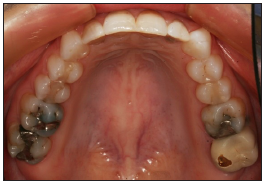

Maxillary arch view

Retractors are required to capture images of the maxillary arch. A high quality mirror should be used to capture reflected image.

The facial surfaces of the central incisors should be visible near the edge of the image.

Lips and mirror edges views should not be visible. The nose and mandibular teeth should not appear in image.

To eliminate fog on the mirror, warm the mirror in hot water ahead of time and ask the patient to breathe through their nose. Hitting the mirror with a light stream of air while taking the photo may be helpful as well.

Capture the image at approximately 45 degree angle to the mirror surface. The placement of mirror should allow for the facial and lingual surfaces to be seen at the same time.

Show as many teeth as possible. The central incisors to the mesial of the second molars should be visible. The anterior teeth must be clearly shown. Maxillary teeth and facial and lingual embrasures should be visible.

Image may be captured from in front of the patient, with patient partially inclined or directly behind the patient with patient fully reclined.

Focus on the reflected image of the premolars.

Adjust the focal length as needed to frame the maxillary arch.